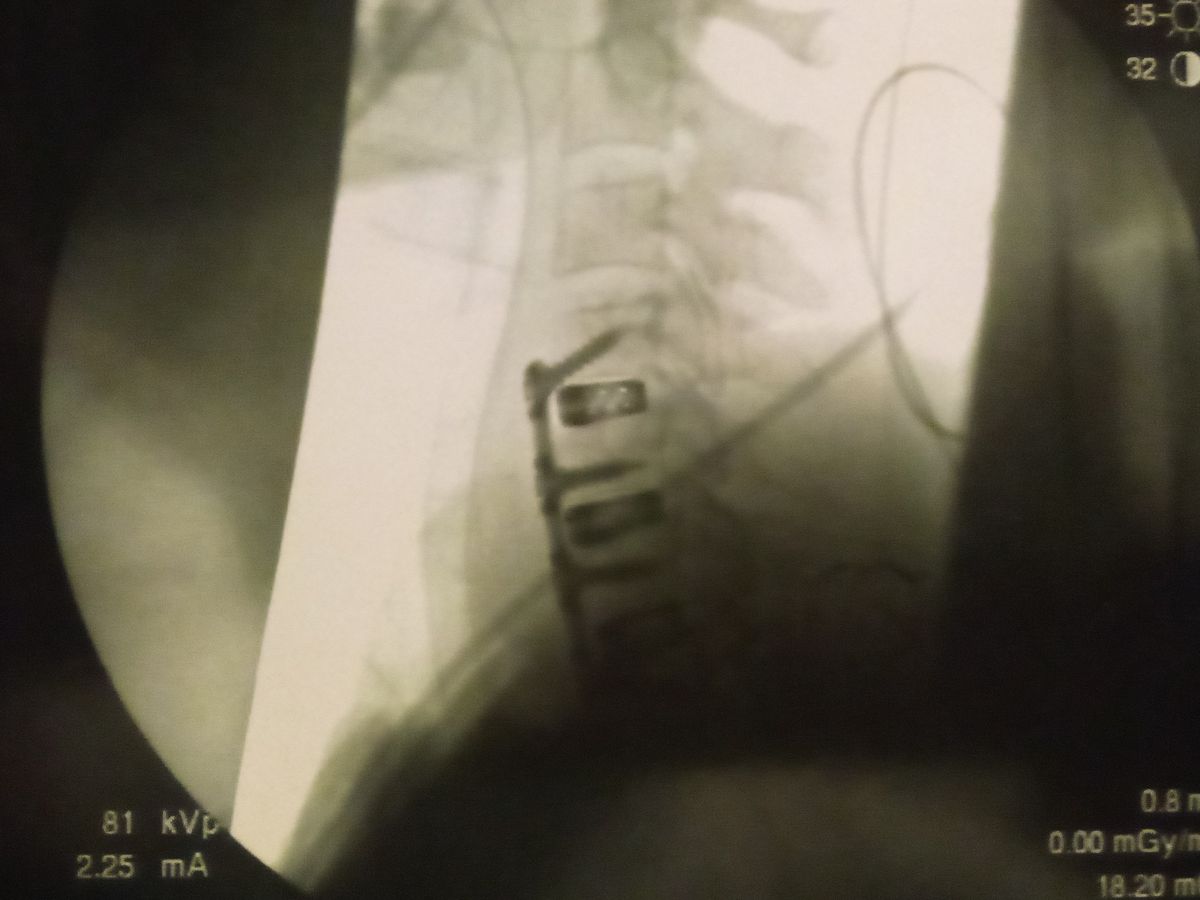

- Hello we are the Kersey family. Recently my husband TD had spinal dissection surgery leaving him unable to work his job he's had for the last ten years,for the next 12-18 weeks at minimum. We are a loving family of 8 with 6 beautiful children ages ranging from 4yrs to 16. We are kindly asking for any help financially as we push through these next trying months of rehab, till my husband is fully recovered back on his feet and can take care of us like he always has! Any help at all would lighten the burden during these tough times ahead, with bills, school clothes, mortgage, supplies etc. and be greatly appreciated. Thank you for your time an thoughts.